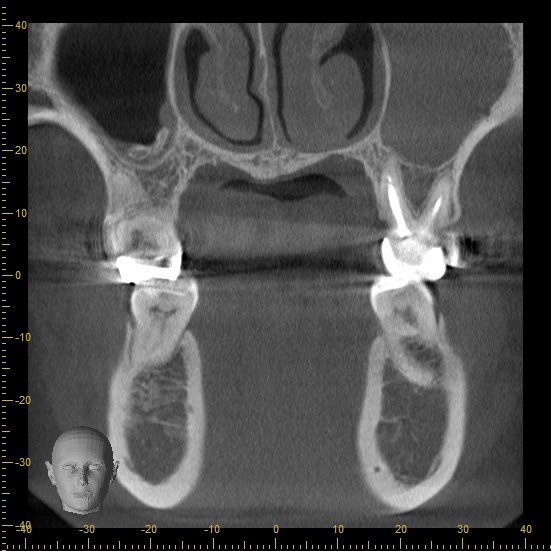

原因を特定し診断するため、追加でCT撮影を行います。

3方向から見た画像です。

下の奥歯の周囲が黒く抜けているのが分かるでしょうか。

通常歯の根は骨に覆われているため、根の周囲が白く見えます。

この部分は菌により骨が溶けてしまい骨の硬さが弱くなることでレントゲンで黒く見えてきています。

この状態になっていると神経を取る治療、根管治療が必要になります。

歯周病に関しては親知らずが影響して、歯周ポケットが深くなってしまっている可能性が高いと考えられます。

将来的に親知らずの抜歯をおすすめしました。